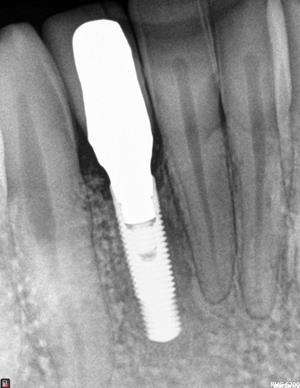

Bone Loss from Improperly Performed Implant Surgery When an implant is improperly placed at the wrong angle or outside of the bone, the bone can be irreparably damaged. Another implant was planned without repairing the failed site - and it, too, would have failed.

Mr. O presented after his general dentist’s implant failed and intended to place a new one at the same damaged site (Fig. 1). We first placed a bone graft with growth factors to rebuild the defect, allowed healing, then used “virtual reality” planning and a custom surgical guide to place the replacement implant with pinpoint accuracy.

Fig. 1: Bone Graft Placed at Failed Implant Site